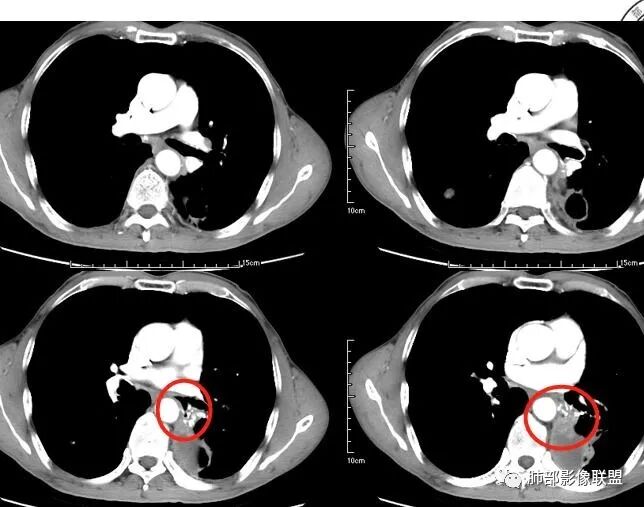

老年男性,咳嗽,咳痰带血2月,左下肺可见一团块影,深分叶,胸膜牵拉,可见坏死,坏死边界清,考虑恶性,双肺多发散在结节影,可见分叶,空洞,胸膜牵拉,考虑转移瘤;

患者老年男性,咳嗽、咳痰、痰中带血伴胸闷2月余。长期大量吸烟史。查肝肾功能、血糖、血脂、心肌酶、电解质、血沉、C反应蛋白、抗“O”、类风湿因子、抗核抗体谱无明显异常。肿瘤标志物提示NSE、CYFRA21-1稍升高。胸部CT:肺气肿背景,左肺下叶后基底段不规则肿块影,见支气管截断,内见大片状低密度区及部分血管影,增强轻度强化,远端空洞形成。双肺多发不规则实性结节影、见毛刺、胸膜牵拉及血管集束,结节内见空洞形成,部分可见血管影,多位于胸膜下。双肺见多发肺大泡。综合考虑左下肺恶性病变并双肺转移。鳞癌或淋巴瘤可能。鉴别血管炎性病变及真菌感染。

张延军:双肺多发结节,空洞影,后者洞壁厚薄不均匀,部分腔内丝丝落落,呈分叶征,边缘见毛刺影,病灶大部分位于胸膜下,与血管相连,右肺下叶前基底段结节近段支气管截断,远端见空腔。左肺下叶病灶密度不均,背段支气管壁增厚,管腔狭窄。考虑1.双肺下叶占位性病变伴肺内空洞性转移 2.多原发的占位 3.肉芽肿性血管炎代排。

本病例左肺下叶肿块,有深分叶、毛刺、胸膜牵拉凹陷、支气管截断及纵隔内淋巴结肿大等征象,都均支持病灶为恶性,如腺癌,而且叶间裂的多发结节也提示是腺癌来源可能大;双肺多发结节、肿块,大部分病灶有分叶、毛刺及胸膜凹陷的恶性征象,与原发肿瘤本身的性质有关,所以应该与左肺下叶肿块同源,而且双肺多发病灶内空洞也具有多样性;